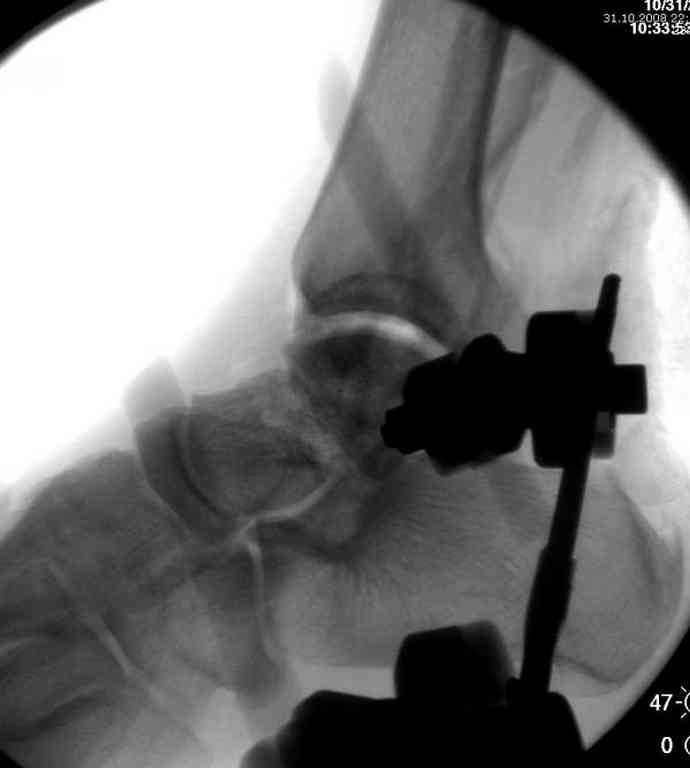

Второй случай прооперирован вчера.

10 дней назад поступил с открытым повреждением медиальной лодыжки и переломо вывихом таранной кости. Ургентно сделана репозиция с наложением наружного фиксатора + Irrigation&Debridment.

Во время репозиции выявили повреждение заднего сухожилия м. тибиалис и задней большеберцовой артерии. Медиальную рану удалось закрыть частично и установлен вакуум.

Дважды провели Irrigation&Debridment с заменой вакуума.

Вчера провели фиксацию.